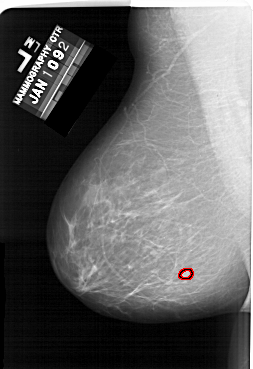

A_1634_1.RIGHT_CC

RIGHT_CC LINES 5791 PIXELS_PER_LINE 3901 BITS_PER_PIXEL 12 RESOLUTION 43.5 NON_OVERLAY

FILE: A_1634_1.LEFT_CC.OVERLAY

TOTAL_ABNORMALITIES 1

ABNORMALITY 1

LESION_TYPE MASS SHAPE LOBULATED MARGINS MICROLOBULATED

ASSESSMENT 4

SUBTLETY 4

PATHOLOGY BENIGN